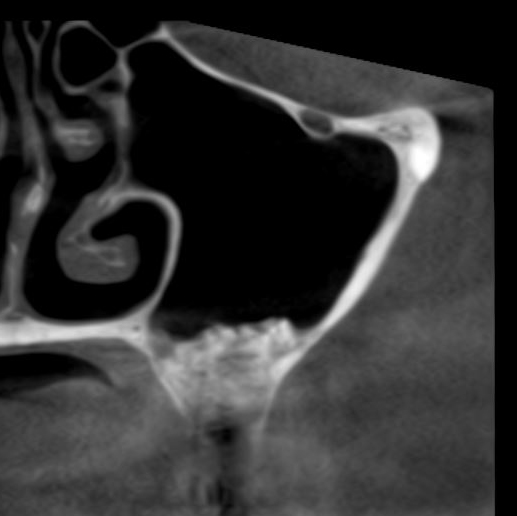

Простой синуслифтинг. Часть III.